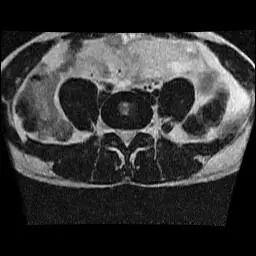

SOP类..........: 1.2.840.10008.5.1.4.1.1.4 (MR Image Storage)

患者姓名........: ABD.ALLAH MOHAMMED ABD.ABLLAH,

检查模态........: MR

图像尺寸........: 256 x 256

像素数组维度.....: 2

像素数组形状.....: (256, 256)

图像帧数........: 1

协议名称........: L.Spine Routine*/4

检查部位........: (缺失)

切片位置........: -4.845304012

test.jpg